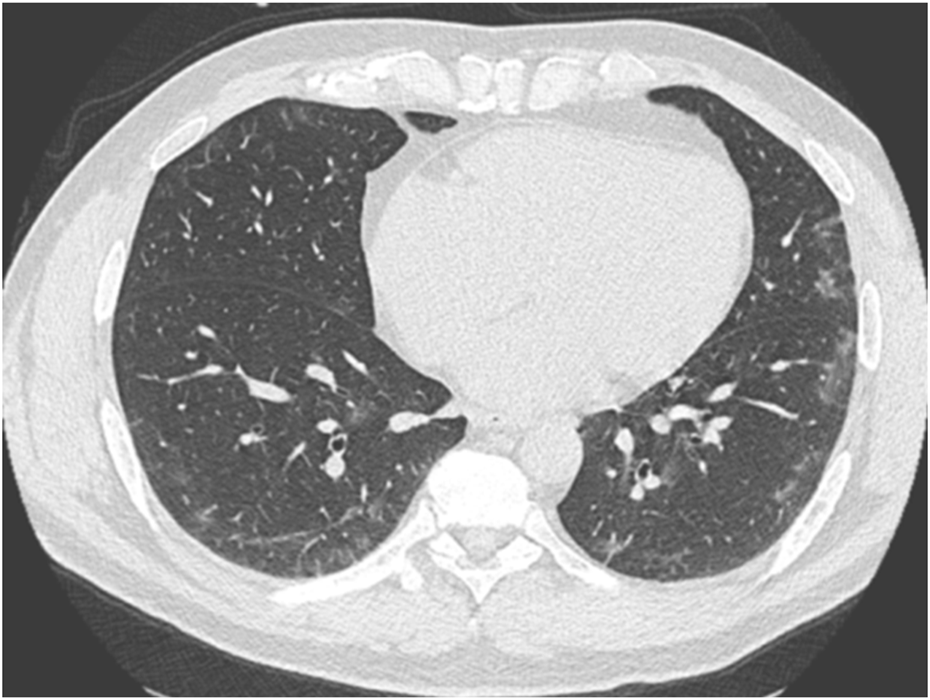

Twenty-four subjects (16.8%) had COVID-induced pulmonary injury on follow-up chest CT. 13 (54%) were in group 1, 6 (25%) in group 2, and 5 (21%) in group 3 (Table 1). The lesions affected less than 10% of the lung volume and were bilateral. They were non-systematized ground-glass opacities (Figure 2), with a sub pleural localization, mainly in the basal areas. Of these subjects, only 3 also had abnormal spirometry. To ensure that the lesions had disappeared, a follow-up CT scan was systematically performed within 3 months after the first CT scan.

FIGURE 2

Asymptomatic diver with a chest CT scan performed 1 month after a positive PCR test. A characteristic appearance of very mild COVID-19-related lung involvement with limited bilateral ground glass opacities can be noted.

In addition, chest CT scans have shown abnormalities in patients who were asymptomatic at the time of the FTD assessment. These ground-glass abnormalities were suggestive of lesions associated with COVID-19 infection, but were also quite similar to lesions seen in immersion pulmonary edema. Therefore, it is legitimate to question the possible consequences of exposure to immersion in this context of subclinical lung injury. These CT abnormalities are probably a risk factor for pulmonary barotraumas during diving. However, indeed, we cannot calculate the risk.